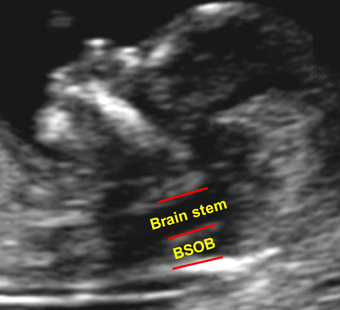

In the first-trimester the Arnold-Chiari II malformation is manifested in compression of the fourth ventricle (intracranial translucency). In the mid-sagittal view of the fetal face at 11-13 weeks the lower part of the fetal brain between the sphenoid bone anteriorly and the occipital bone posteriorly can be divided into the brain stem in the front and a combination of the fourth ventricle and cistern magna in the back. In most cases of open spina bifida the diameter of the brain stem is increased, the distance between the brain stem and the occipital bone (BSOB) is decreased and the ratio of the brain stem to BSOB is above 1.0.

Brain in spina bifida